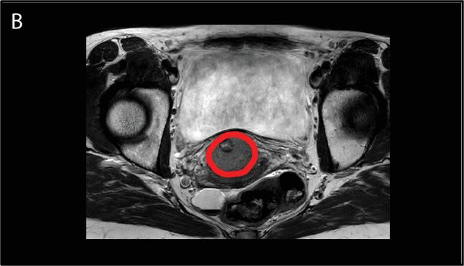

תזרים העבודה למתן טיפול בהיפרתרמיה מקומית-אזורית (locoregional) כולל מספר שלבים. ראשית, היפרתרמיה צריכה להיות מתוכננת ברצף עם מתן הקרנות. באופן כללי, היפרתרמיה ניתנת פעם בשבוע זמן קצר לפני או אחרי פרקציות ההקרנות. במקרים חריגים מסוימים, היפרתרמיה ניתנת פעמיים בשבוע, עם לפחות 3 ימים בין כל מפגש כדי למנוע אינדוקציה של עמידות תרמית. כדי להשיג את התועלת המרבית של היפרתרמיה כרדיוסנסטיזטור, מרווח הזמן בין הקרנות להיפרתרמיה צריך להיות פחות משעה אחת. במרכז של החוקרים, לאחר מיקום של צנתרים פולשניים מינימליים להחדרת בדיקות טמפרטורה בנרתיק, בשלפוחית השתן ובפי הטבעת, נעשה CT תכנון היפרתרמיה (hyperthermia planning CT) של המטופלת על מזרן ההיפרתרמיה ובולוס המים מסביב עם צנתרי הבדיקה התרמית האלה במקומם (איור 2A). CT זה משמש לחלוקה אוטומטית של רקמות בעלי תכולת מים גבוהה לעומת אלו עם תכולת מים נמוכה עבור תכנון טיפול בהיפרתרמיה, כאשר הגידול מותאם על ידי הרופא, בהנחיית ה-MRI שנעשה לתכנון הקרנות (איור 2B). בנוסף, ה-CT משמש לקביעת אילו מנקודות מדידת הטמפרטורה מייצגות גידול ואילו רקמה נורמלית לבקרת טמפרטורה אופטימלית במהלך הטיפול. מטרת תכנון הטיפול בהיפרתרמיה היא לקבוע את הגדרות המכשיר האופטימליות וכתוצאה מכך חימום טוב של הגידול תוך הימנעות מחימום יתר של רקמות רגילות (איור 2A).

להלן איור A2: תכנון טיפול היפרתרמיה כאשר הגידול בצוואר הרחם מתואר באדום בסריקת CT היפרתרמיה ייעודית עם בדיקות תרמיות במקום שנעשו ישירות לפני טיפול ההיפרתרמיה. מוצגות גם הנקודות החמות (האזור האדום) והקרות (האזור הירוק).

להלן איור B2: סריקת MRI כסיוע לקווי מתאר המתאימים של הגידול ב-CT